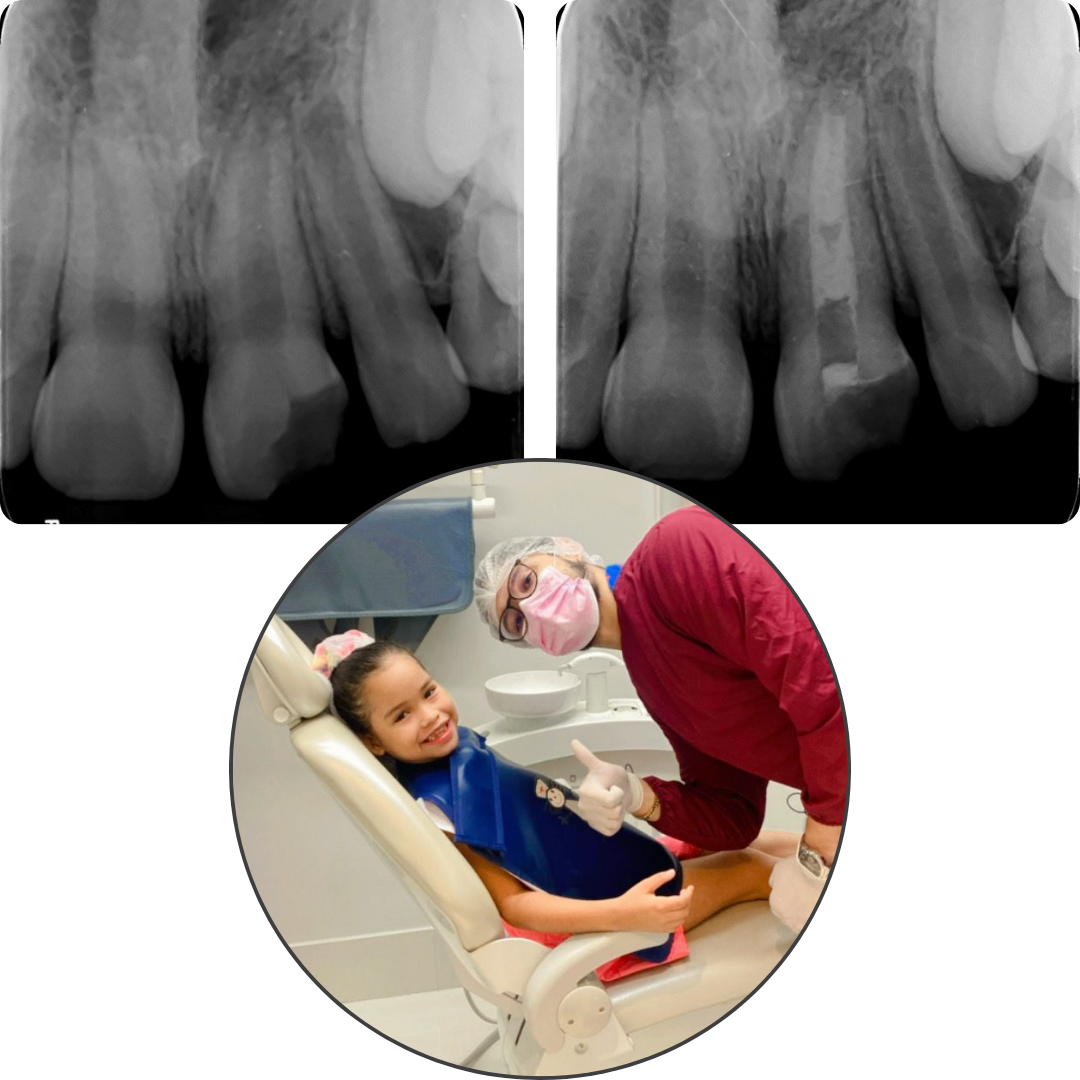

*Imagens clínicas e radiográficas documentadas podem ser apresentadas em consulta, respeitando o sigilo e ética profissional.

Tratamento endodôntico (adulto e infantil)